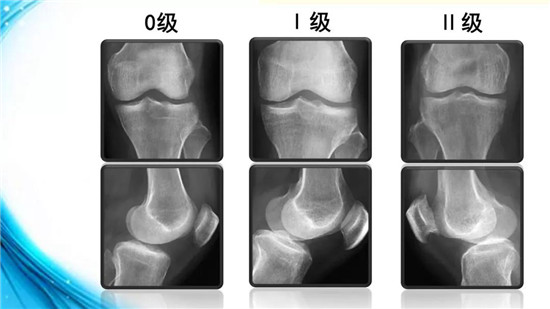

下面,我们来了解一下膝骨性关节炎的分级、分型与分期。根据X线所示,可对膝骨性关节炎进行分级。

0级为正常膝关节。Ⅰ级关节间隙可疑狭窄,可能有骨赘。Ⅱ级关节间隙轻度变窄,有明显骨赘。

我们看一下Ⅰ级这张片子,可见髁间隆起变尖,那么真的是髁间隆起增生变高了吗?它是变高了,但不是增生导致的变高,而是由于内侧胫股关节压力变大,对应的胫骨关节面出现了微骨折,关节面塌陷,使髁间隆起相对地看起来变高了而以。